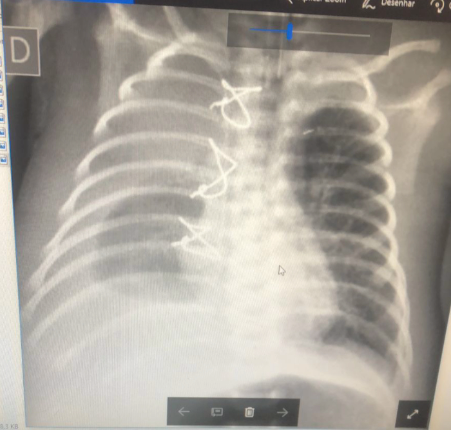

Imagem:

Raio-X de tórax e Ultrassom torácico mostram derrame;

Imagem 02: Derrame pleural volumoso em paciente submetido à correção de Tetralogia de Fallot. Durante a drenagem torácica (imagem do dreno na Imagem 01), foi possível observar o aspecto leitoso do líquido pleural, sugestivo de quilo.

Fonte própria

Eco para avaliar função do VD, estenose ou trombose venosas (do Glenn, por exemplo);